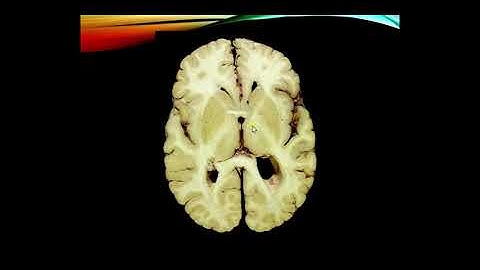

Neoroanatomy Cerebral Cortex part 2